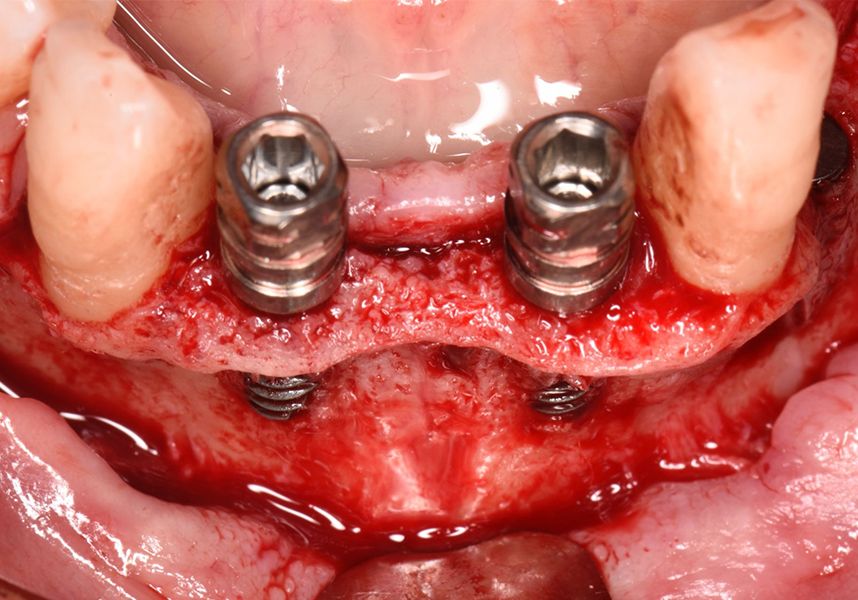

The patient was anesthetized and a flap was made from the distal area of tooth 43 up to 36. Then two Avinent Biomimetic Ocean IC implants of 3.5x10 were inserted in positions 32 and 42.

Respecting the three-dimensionally correct position of the implant led to bone fenestration, leaving the apical part of the apex of the implant exposed almost to the mid-point of its length at 42 and a third in 32.

To treat the defect, bone regeneration was carried out simultaneous to the surgical process, with an autologous bone graft from the patient. In the internal part of the graft we used autologous cortical bone obtained by scraping (Safescraper) and from the biological drilling, at low revolutions and without irrigation, from the other implant beds. In the external layer of the regeneration we used a xenograft (Genoss, Osteogenos) and this was covered with a reabsorbable collagen barrier membrane (Evolution STD, Osteogenos).